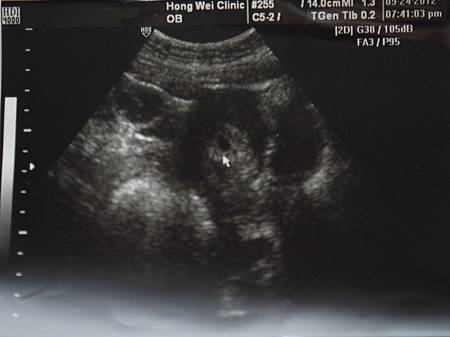

- 9月 24 週一 201221:19

不明駭客入侵

接著就躺上一個小床前方有台螢幕

接著醫生就在我的肚子上塗上冰涼物體

超音波照阿照的

白色箭頭上的黑色不明物體

那物體就是入侵我身體的駭客

醫生:這就是胚胎齁,大約五周齁

大約要六七周才會有心跳齁

所以下禮拜再來照心跳